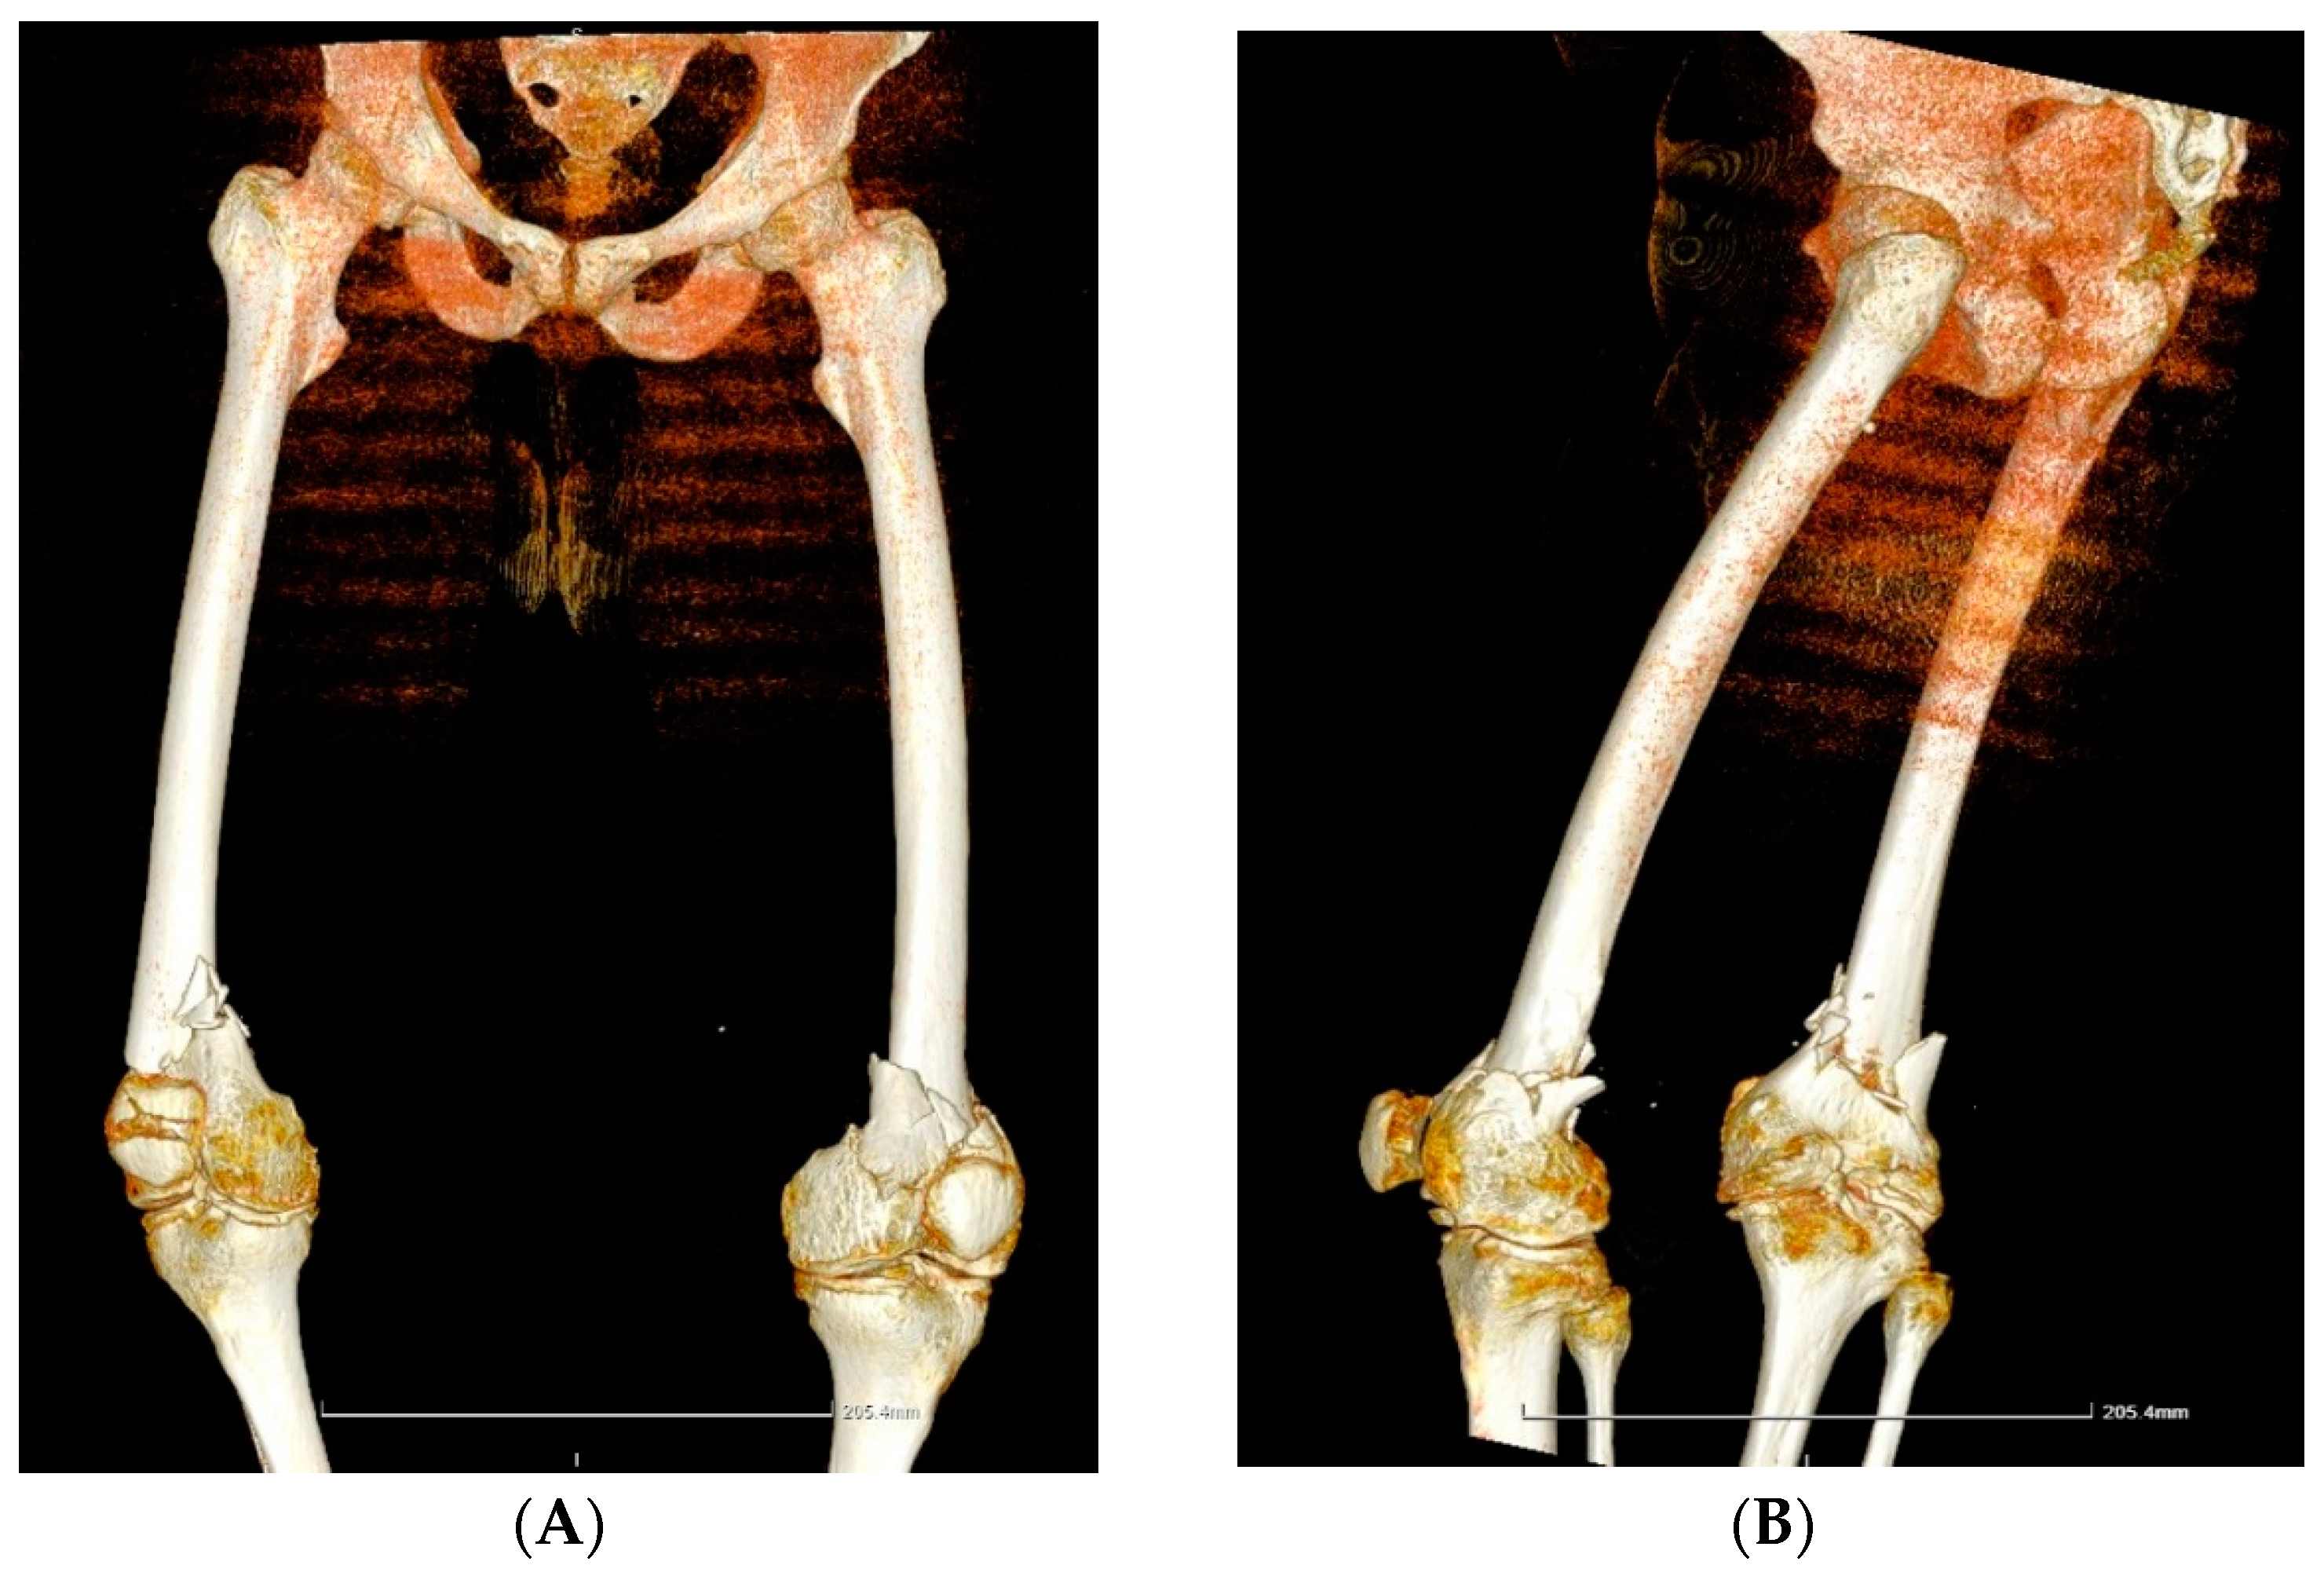

| Case 2. 39-years-old male, with severe haemophilia A | -chronic viral hepatitis C | -post-traumatic bilateral femoral supracondylar fracture | -open reduction and osteosynthesis with plates and screws of the pelvic limb bilaterally | ~1300 mL (4 units pRBCs) | ~40,217.44 € (71.78% for EHL FVIII concentrate) | No | Good, discharge after 21 days |